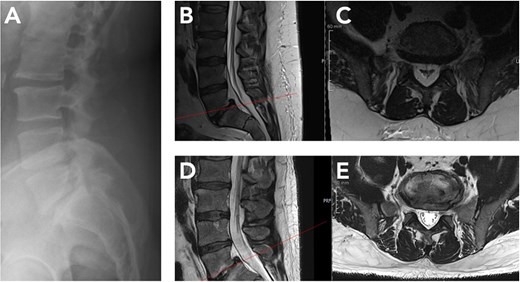

Lumbar magnetic resonance imaging (MRI) demonstrated diffuse epidural fat from L3 to S1 consistent with SEL, with severe thecal sac compression and maximal canal narrowing at L5–S1 as seen in Fig. 1. Initial conservative management with physiotherapy, lifestyle-based weight loss advice, and non-opioid analgesics produced little benefit. Baseline pain was rated 8/10, and he could ambulate less than 500 m before stopping because of neurogenic claudication.

At eleven months, repeat lumbar MRI showed marked regression of epidural lipomatosis (Fig. 2). Epidural fat volume at L3–S1 had decreased substantially, and the previously severe central canal stenosis had resolved, with normalization of thecal sac contour and canal dimensions. No new degenerative changes were detected. Clinically, the patient reported complete resolution of neurogenic claudication and only mild intermittent low back discomfort. In view of the radiologic and clinical improvement, decompressive surgery was deemed unnecessary.

Radiological regression of lumbar spinal epidural lipomatosis (L5/S1) between October 2024 and September 2025. (A) Lateral lumbar spine radiograph (October 2024) showing preserved vertebral alignment without instability but indirect signs of reduced dorsal epidural space at L5/S1. (B, C) Baseline MRI (October 2024). Sagittal and corresponding axial T2-weighted sequence at L5/S1 level demonstrates marked epidural fat accumulation at L5/S1 with compression of the thecal sac. (D, E) Follow-up MRI (September 2025) after massive GLP-1–induced weight loss. Sagittal and corresponding axial T2-weighted image at L5/S1 level shows substantial reduction of epidural fat with re-expansion of the thecal sac.